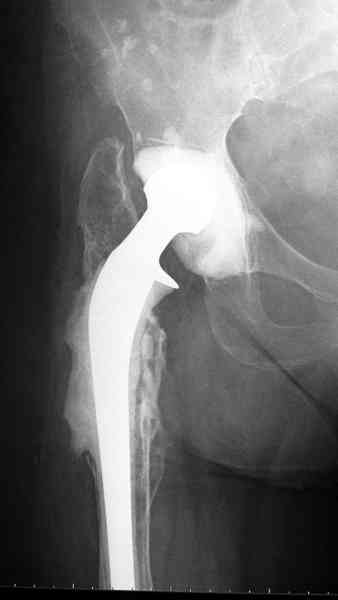

Повторная операция по удалению тотального протеза с irrigation&debridment, канал после очистки цемента обильно промыт и рассверлен римером.

Приготовлен цемент из расчета: Tobramycin 2.4 g (2 флакона), Vancomycin 2 млн (4 флакона) и 2 упаковки цемента с добавлением дополнительного флакона цементной жидкости.

После обработки ацетабулярного компонента, ещё в мягком цементе в полости вертлужной впадины головкой бедренного компонента сделана выемка для головки, чтобы свежий цемент не прилипал к головке. Головку бедренного компонента завернул обычной стерильной фольгой, которую после образования выемки отлепил от головки.

Для спейсера в бедро использовал старый длинный бедренний компонент меньшего диаметра, облепленный со всех сторон цементом с антибиотиком.

и последние снимки.